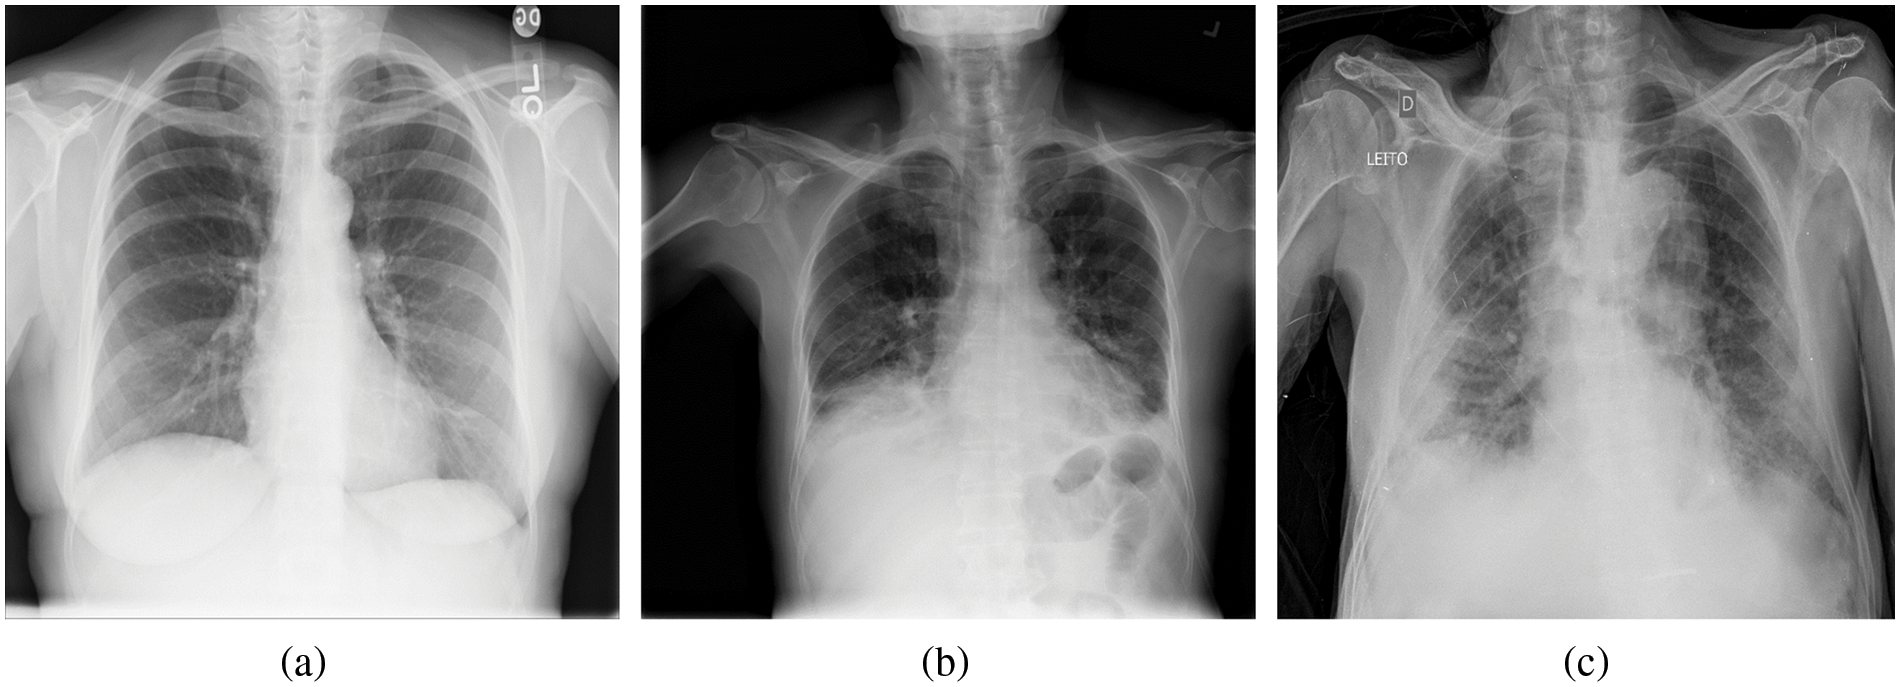

Figure 2: Example of chest X-ray (CXR) images in the COVIDx dataset. (a) Normal or no pneumonia finding, (b) pneumonia infection, (c) COVID-19 viral infection